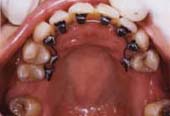

■歯の裏側矯正

歯の裏側に装置をつけますので、外からはまったく見えません。

最近は多くの方が希望される治療方法です。